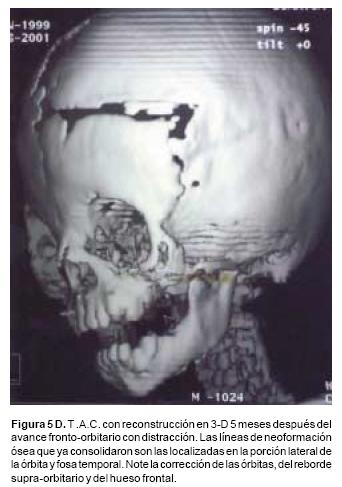

Luego de un periodo de latencia de cinco días, los distractores se activan a un ritmo de un milímetro cada día. Los avances obtenidos en este grupo de pacientes varían entre 16 y 30 mm, en el hueso frontal, de 12 a 25 mm, en el complejo órbito–malar–cigoma y de 10 a 18mm, en el maxilar. Luego de un periodo de consolidación de 10 a 12 semanas, los distractores óseos se retiran bajo sedación.

En todos los pacientes se logró el avance planificado de los segmentos óseos, al corregir la deformidad del hueso frontal, el exorbitismo y en la retrusión del tercio medio en los casos con avance en monobloque. Los avances mayores se obtuvieron en el hueso frontal y variaron entre 16 y 30 mm., mientras que los menores fueron los del hueso maxilar que fluctuaron entre 9 y 16 mm. (Cuadro I). Radiológicamente los controles postoperatorios tempranos mostraron inicialmente áreas de hipodensidad ósea, que al final del periodo de consolidación cambiaron a áreas de densidad ósea radiológica normal, lo que significa neoformación de hueso. Las áreas de hueso neoformadas que consolidaron en forma más rápida, son las ubicadas en las líneas de osteotomía de la unión pterigomaxilar, pared lateral de la órbita y unión frontoorbitaria. Las áreas que más tardaron en consolidar incluye la porción lateral y superior del hueso frontal.

También los controles radiológicos durante el proceso de distracción mostraron que no se produjo la creación de espacios muertos intracraneanos durante los avances. En todos los pacientes con sinostosis bicoronal el avance frontoorbitario produjo excelentes resultados estéticos dando una nueva forma a la región frontal y proyectando mejor el reborde supraorbitario. En los niños con enfermedad de Crouzon y síndrome de Apert, se corrigió en forma muy satisfactoria el exorbitismo al resolver las graves exposiciones corneales (Figuras 5 A, B, C, D, E, F, G, H), en los que se utilizó el avance simultáneo del tercio medio, este cambio óseo corrigió muy satisfactoriamente la retrusión del mismo, ampliando la vía aérea y resolviendo en muchos casos grandes problemas ventilatorios durante el sueño (Figuras 6 A, B, C, D, E, F). Los pacientes con plagiocefalia corrigieron significativamente la deformidad frontoorbitaria y los tejidos blandos suprayacentes se adaptaron a la nueva estructura ósea. La clásica órbita de arlequín de estos niños producida por la sinostosis del frontal con el esfenoides, inmediatamente se ve corregida en su forma y su configuración se hace muy similar con la órbita contralateral (Figura 7)(Fig. 7a, 7b, 7c, 7d, 7e, 7f, 7g) (Cuadro II).